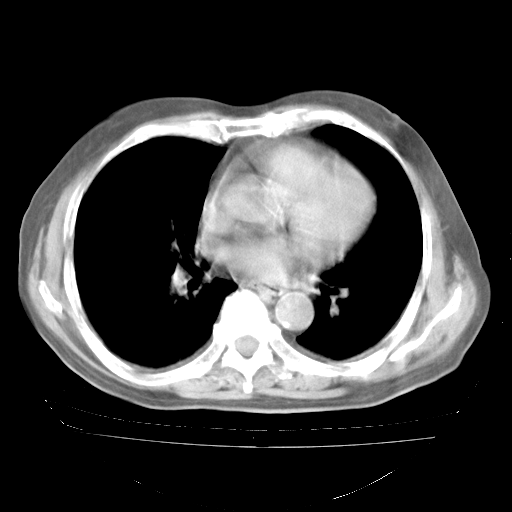

4月28日肺部CT——再次出现类似去年5月9日——透光度降低,“间质性”改变。

4月28日肺部CT